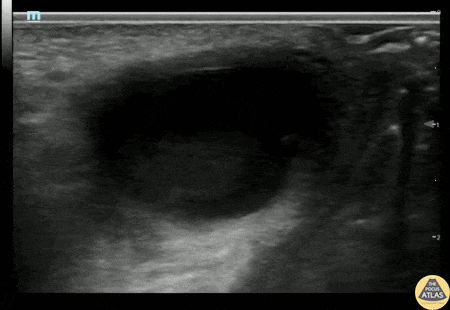

OB/Gyn - Bartholin's Abscess

20s F with past medical history of multiple bartholin gland abscesses requiring drainage presented with genital pain and swelling. I&D of the abscess was attempted which was initially unsuccessful, so POCUS was performed to confirm the location of the abscess. Gynecology was then consulted for drainage and was able to successfully drain the abscess. Alexandrea Netto PA, Denver Health and Hospital Authority Katie McCabe MD, Attending Physician, Denver Health Residency in Emergency Medicine